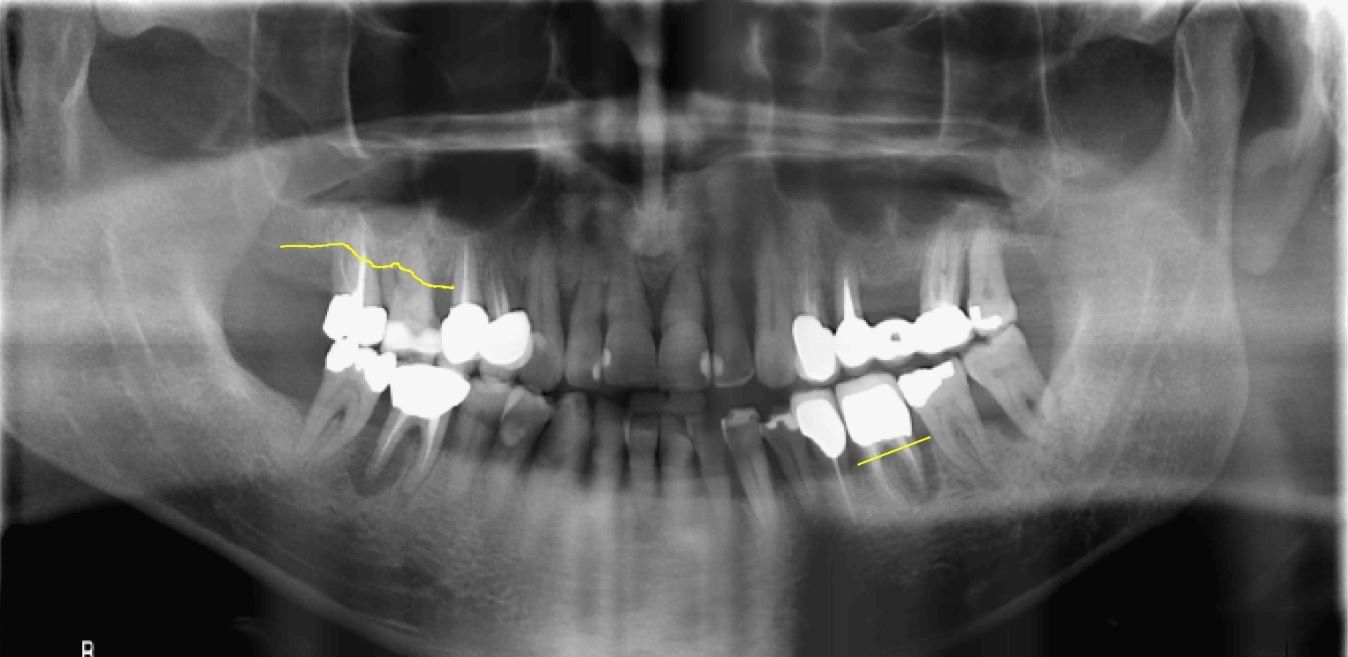

Fig. 2_Radiografia panoramica pre-operatoria di uno dei pazienti inclusi al tempo della chirurgia.

Fig. 7_Radiografia panoramica a 3 anni dall’intervento in cui si apprezza il mantenimento dei livelli ossei peri-implantari.Nuovo paragrafo